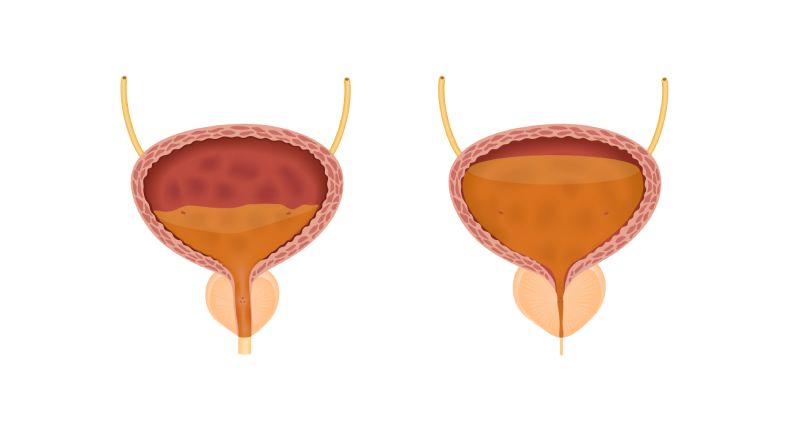

Стриктура (сужение) уретры — это уменьшение просвета мочеиспускательного канала из-за рубцевания его стенки. Болезни подвержены преимущественно мужчины, у женщин патология встречается редко. Это происходит, в том числе, в силу анатомических особенностей. Мужской мочеиспускательный канал более протяжённый и узкий по сравнению с женским.

Основной признак болезни — затруднённое мочеиспускание. При стриктуре уретры выраженность симптомов зависит от степени сужения её просвета.

При полном закрытии просвета уретры развивается острая задержка мочеиспускания — состояние, при котором не удается помочиться. Патология требует неотложной медицинской помощи.

Процесс начинается с повреждения слизистой, выстилающей уретру, или окружающего её губчатого (спонгиозного) тела. Во время заживления в тканях формируются фиброзные участки. Они состоят из волокнистой, аномально плотной соединительной ткани с рубцовыми изменениями. Из-за образования рубцов уменьшается просвет мочеиспускательного канала. Ухудшается проходимость уретры.

Фиброзная ткань менее эластична. Под давлением мочи в стенке уретры могут появляться микротрещины, через которые жидкость просачивается в губчатое тело. Это способствует увеличению зоны поражения. Изменения прогрессируют, процесс распространяется вдоль уретры или вглубь губчатого тела.

Сужение уретры опасно своими последствиями. Постоянное давление мочи на изменённые ткани создает условия для проникновения инфекции. Также травмируются стенки мочеиспускательного канала и вышележащие органы.

- Гидронефроз. Нарушение выхода мочи приводит к повышению давления жидкости в мочевом пузыре, а затем к нарастанию внутрипочечного давления. Паренхима (основная функциональная ткань почки) страдает из-за постоянного сдавливания. Постепенно возникает атрофия тканей, развивается почечная недостаточность. При отсутствии лечения почки со временем могут утратить работоспособность.

- Острая задержка мочеиспускания. Осложнение развивается, если просвет уретры закрывается полностью. Пациент не может опорожнить мочевой пузырь при сильных позывах к мочеиспусканию, испытывает сильную боль внизу живота. Состояние требует срочной медицинской помощи.

- Камни в мочевом пузыре. Конкременты постепенно формируются из-за застоя мочи на фоне проблем с мочеиспусканием.